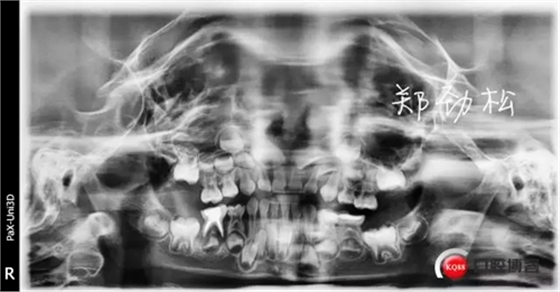

我的病例三 7E牙髓炎